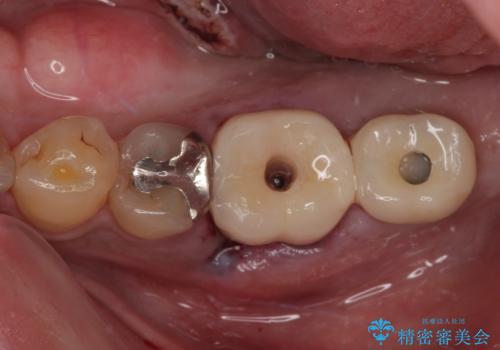

- 以前、咬合力の強さで歯の神経が失活してしまい、当院にて根管治療を行った患者様ですが、今度は咬合力の影響で歯根が破折してしまった患者様です。

歯根が破折してしまった歯は抜歯が必要となり、特に咬合力が強い方ですと、インプラント治療による治療がお勧めとなります。

従来のインプラント治療ですと、抜歯をしてからその部分の骨が回復するまで数か月待機し、その後インプラント埋入、生着を待って土台の頭出し手術、仮歯の装着となるため、咬合回復するまでに半年かそれ以上の期間が必要となってしまいます。

咬合力の影響で歯が壊れてしまう方の場合、長期間欠損が続くと、連鎖するように他の歯が壊されてしまうリスクがあるため、抜歯即時インプラントにより、治療期間の短縮を図ることとしました。